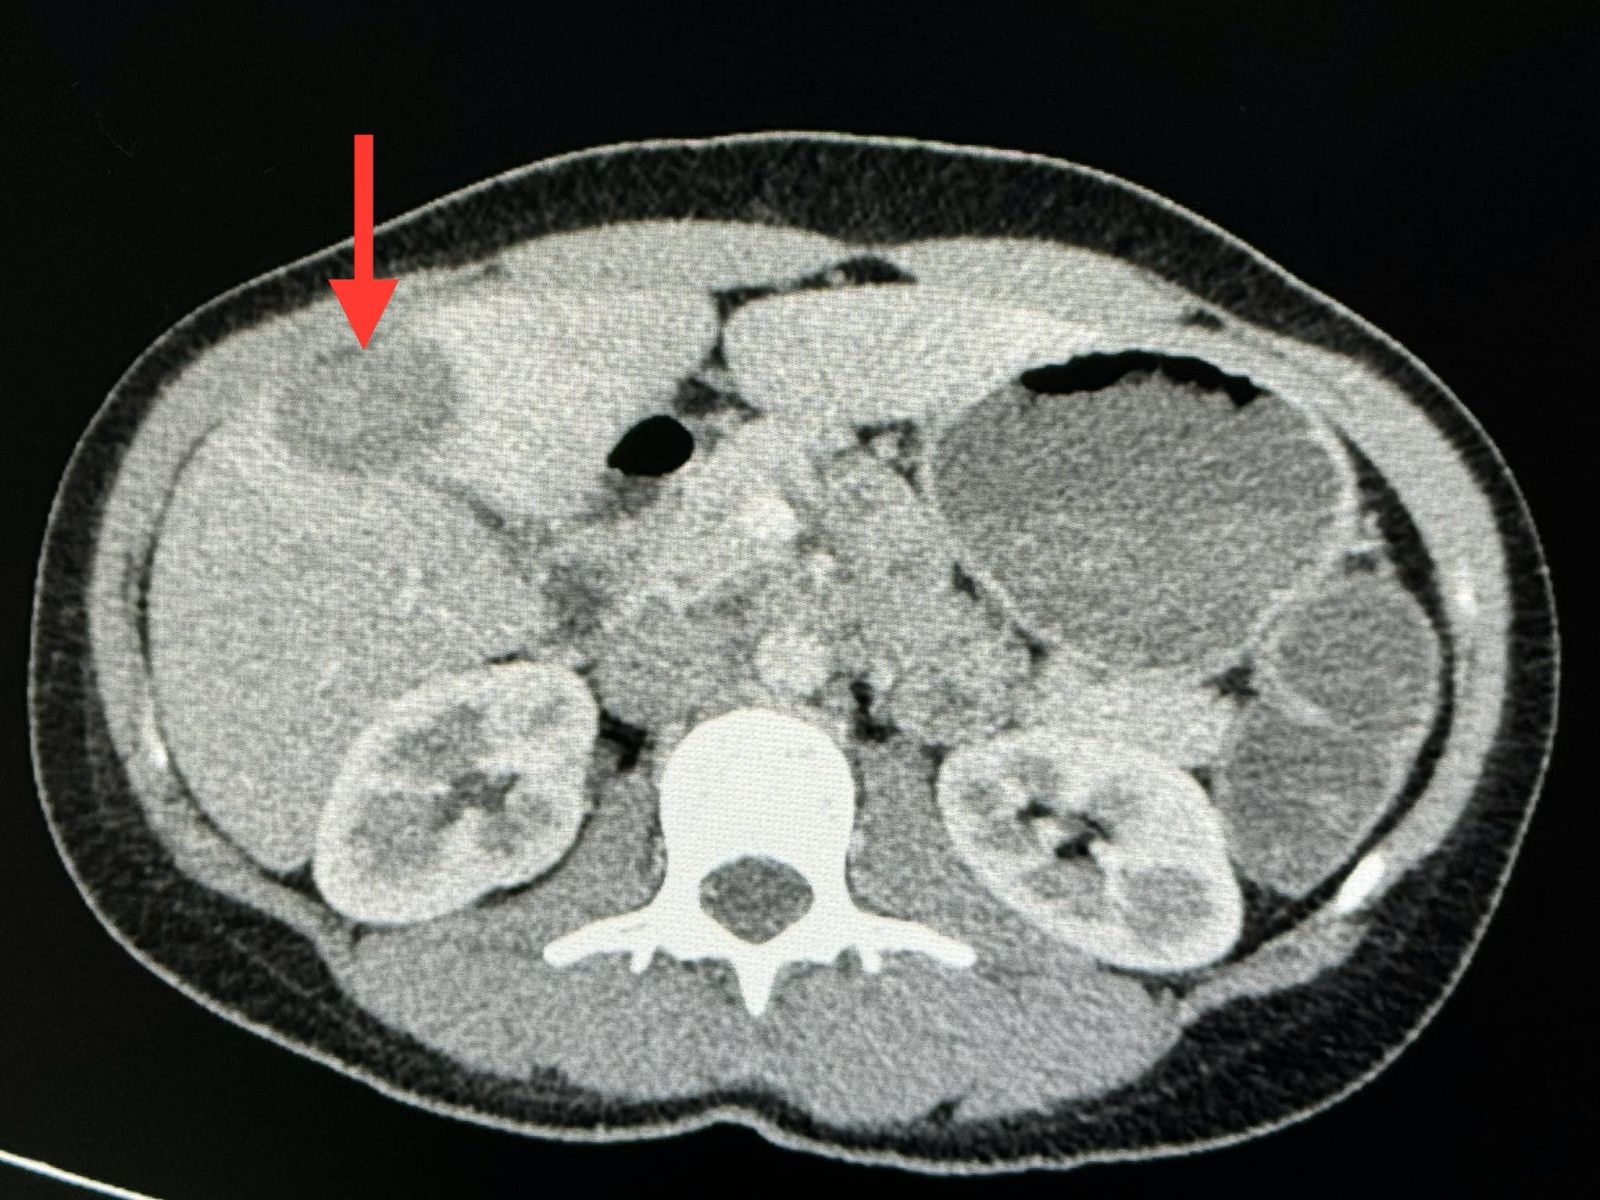

ตรวจร่างกายปกติ ฟังปอดปกติ ระดับออกซิเจนในเลือดปกติ เจาะเลือดเม็ดเลือดแดงและเกล็ดเลือดต่ำเล็กน้อย ค่าตับไต ปกติ ค่ามะเร็งทุกตัวปกติ ทำคอมพิวเตอร์ปอดและช่องท้อง พบจุดเล็กๆ ในปอดขนาด 0.8 เซนติเมตรกระจายทั่วปอด และมีก้อนในตับขนาด 3.4 เซนติเมตร ได้ทำการเจาะเนื้อในตับ ย้อมและเพาะเชื้อ ไม่พบเชื้อราและเชื้อวัณโรค ส่งชิ้นเนื้อตรวจพยาธิวิทยา พบ Epithelioid hemangioendothelioma ติดตามผู้ป่วยนับจากวันที่มีเอกซเรย์ปอดผิดปกติ ถึงปัจจุบัน 6 เดือนแล้ว ผู้ป่วยยังไม่มีอาการ